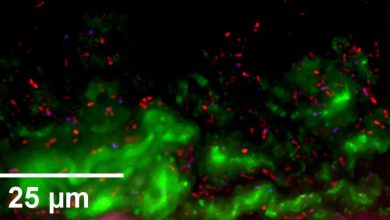

Modelos de nariz em miniatura podem ajudar a prevenir infecções e promover a saúde nasal

Imagem de microscopia de imunofluorescência de S. pneumoniae (vermelho) incorporado em muco secretado por HNO (verde) após 6 horas de…